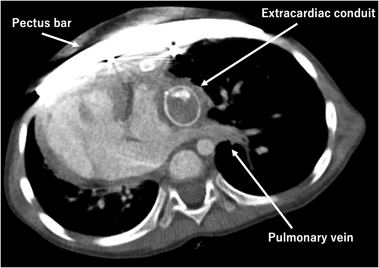

The postoperative course was uneventful, and the patient was discharged home on the 15th postoperative day. Postoperative computed tomography scan revealed repaired pectus excavatum without compression of the conduit, the IVC, nor the pulmonary veins. Haller index improved to 2.80 (Fig. 3).

In our case, simultaneous repair was considered necessary to secure the Fontan pathway by correcting the pectus excavatum; compression to the Fontan route and the pulmonary veins were avoided. As anticipated preoperatively, postoperative CT revealed that the Fontan conduit occupied a considerable space within the thoracic cavity. The pulmonary veins appear better structured than preoperative state.